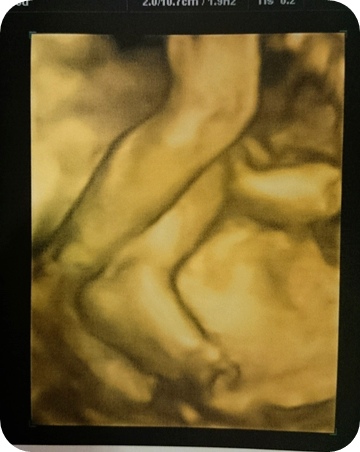

我應該再兩三個星期就可以下蛋了....

結果就是.........我的小孩長太快....明明只有37周...卻是40周的大小...

看朋友都在分享小孩子的照片了,我也期待我的長腿妹快點生出來。

順帶一提:我不是懷雙胞胎....我只是給我女兒住豪宅...所以肚子比較大一點啦....哈哈哈哈